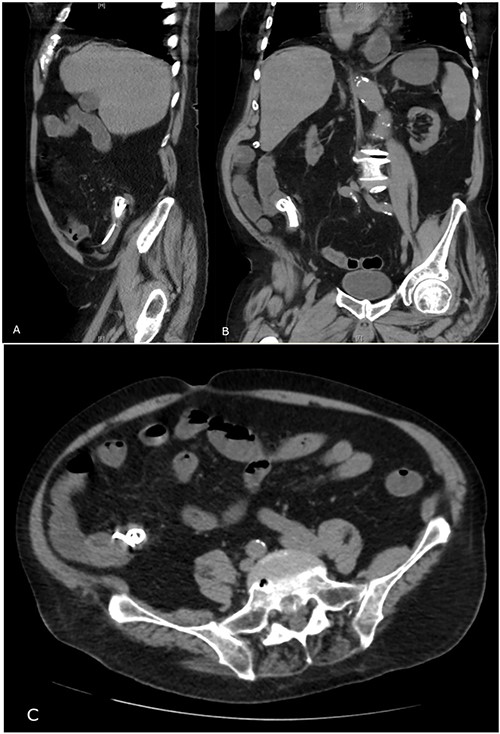

Abdominal CT showing migrated biliary stent in sagittal (A), coronal (B) and transverse (C) views.

After a multidisciplinary consultation involving medical, geriatrics and surgical teams, the patient and family collectively decided for conservative management given age and high-risk multiple comorbidities. He was managed with intravenous fluids, broad spectrum Gram positive and Gram negative intravenous antibiotics, nasogastric tube and an indwelling catheter for 48 h. He progressed with minimal pain over the next 24 h and passed flatus. Subsequent plain abdominal radiography 2 days after presentation confirmed the presence of migrated metal and plastic biliary stents in the terminal ileum with dilated loops of small bowel suggestive of ongoing bowel obstruction (Fig. 3). After 5 days of not opening bowels and ongoing pain, he was transferred back to a nursing home facility with palliative care services in place. The patient passed away 3 weeks after transferring back to the nursing home facility with a suspected bowel perforation and no documentation of the stents having been passed.